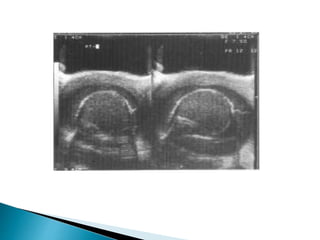

 Doppler ultrasound with sensitivity of 85% in the

diagnosis of torsion reduced vascularity

(absence or poor colour flow, reduced peak

systolic velocities) compared with the unaffected

side.